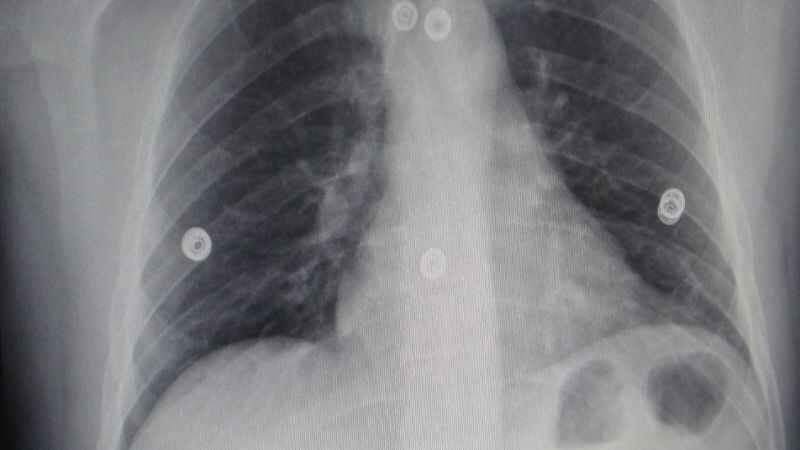

Enfeksiyon sonrası geçmeyen öksürük şikayetlerinde yaşanan artış, uzmanları harekete geçirdi. ''Endişelenecek bir durum yok'' uyarısında bulunuldu.

Tüm Türkiye’de olduğu gibi Van’da da kış ayları itibariyle viral üst solunum yolu enfeksiyonlarında artış yaşandı. Enfeksiyon sonrası kişilerin yaşam kalitesini büyük ölçüde etkileyen ve haftalarca süren öksürük şikayetlerinin artışı da dikkat çekti. Uzmanlar ise 8 haftadan az süren öksürük şikayetleri için bitki çayı ve sık sık ılık su tüketimini tavsiye ederken, hastaların öksürükle birlikte; kan tükürme, ateş, nefes darlığı şikayetlerinde de bir sağlık kuruluşuna başvurmalarını önerdi.

İHA muhabirine konuşan Göğüs Hastalıkları Uzmanı Dr. Siahmet Atlı, mevsimsel geçişlerde solunum yolu enfeksiyonlarının arttığını belirtti. Özellikle bu yıl kış aylarında solunum yolu enfeksiyonlarının biraz daha fazla görüldüğünü hatırlatan Dr. Atlı, “Çoğunlukla solunum yolu enfeksiyonlarının neden olduğu burun akıntısı, hapşırma, öksürük, genel vücut ağrısı ve ateş gibi şikayetlerle hastalar başvuruyor. Daha çok rinovirüs, Respiratuar Sinsityal Virüs (RSV), İnfluenza virüsü gibi etkenler sebep olmaktadır. Tabii buraya kadar her şey normal. Ancak kişiler enfeksiyonu geçirdikten sonra geçmeyen bir öksürük başlar. Bu öksürük özellikle 3 haftadan fazla ve 8 haftadan az oluyor. Fakat bazı hastalarımıza 8 haftadan fazla da olabiliyor. Bu da gereksiz acil başvurularını artmaktadır. Bu rahatsızlık; yaşam kalitesini bozmakta, çoğu hastamızda baş ağrısı, uyku bozukluğu, idrar kaçırma, göğüs ağrısı gibi hatta çok öksürmekten kaynaklı boğazda tahriş ve balgamında kan gelme şikayetlerine neden oluyor” dedi.

Pandemiden sonra virüslerin uzun süredir az görüldüğünü ve bu kış aylarında da bir patlama yaşanmasına sebep olduğunu düşündüklerini dile getiren Atlı, “Bunlar viral enfeksiyonlar olduğu için uzamış öksürüğe sebep oluyor. Özellikle ocak ve şubat aylarında polikliniğimize başvuruların yaklaşık yüzde 50’sinden fazlası sadece enfeksiyon sonrası öksürüktü. Grip, nezle, soğuk algınlığı adına ne dersek diyelim. Ondan sonra başlayan öksürük 3 ila 8 hafta arasında sürüyor ve yüzde 80’ine kadar kendi kendinden geçebiliyor. Kişinin burada panik yapmasına gerek yok. Ancak 8 haftadan fazla bir süre devam ederse ve üzerine balgam, kan tükürme, ateş, nefes darlığı eklenirse o zaman bir uzmana başvurmaları gerekmektedir” diye konuştu.